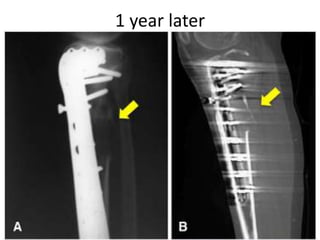

1 year later

AUG 2010

JAN 2013

• MAY 2013

• DENOSUMAB started

• 360 mg subcutaneous dose

• Followed by 120 mg every month

OCT 2013

• Pain around knee joint diminished

• Further resection ??

• Patient refused

• Clinical improvement persisted until jan 14

• Presented with Rapidly growing painful

palpable mass

• Open biopsy : high grade sarcoma

• A/K amputation